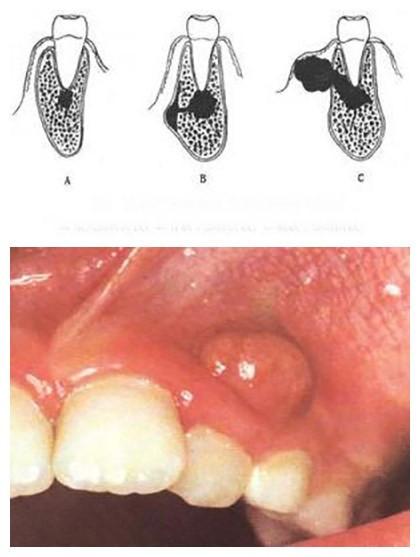

其实不然,大多数牙龈脓包是由乳牙牙根的慢性炎症也就是慢性根尖周炎引起的,下面图片中黑色的部分就是牙根发炎所形成的脓液示意图,其脓液经历了由少到多的发展过程。

而根尖周炎大都是由牙髓炎发展而来,当牙髓炎没有得到及时治疗,牙神经感染坏死,炎症向牙齿根部发展,造成牙根周围组织感染甚至化脓,脓液聚集太多而没有排出通道时,脓液就会顺着牙根周围的疏松组织扩散到牙龈这个部位,导致牙龈起包,称为化脓性根尖周炎。